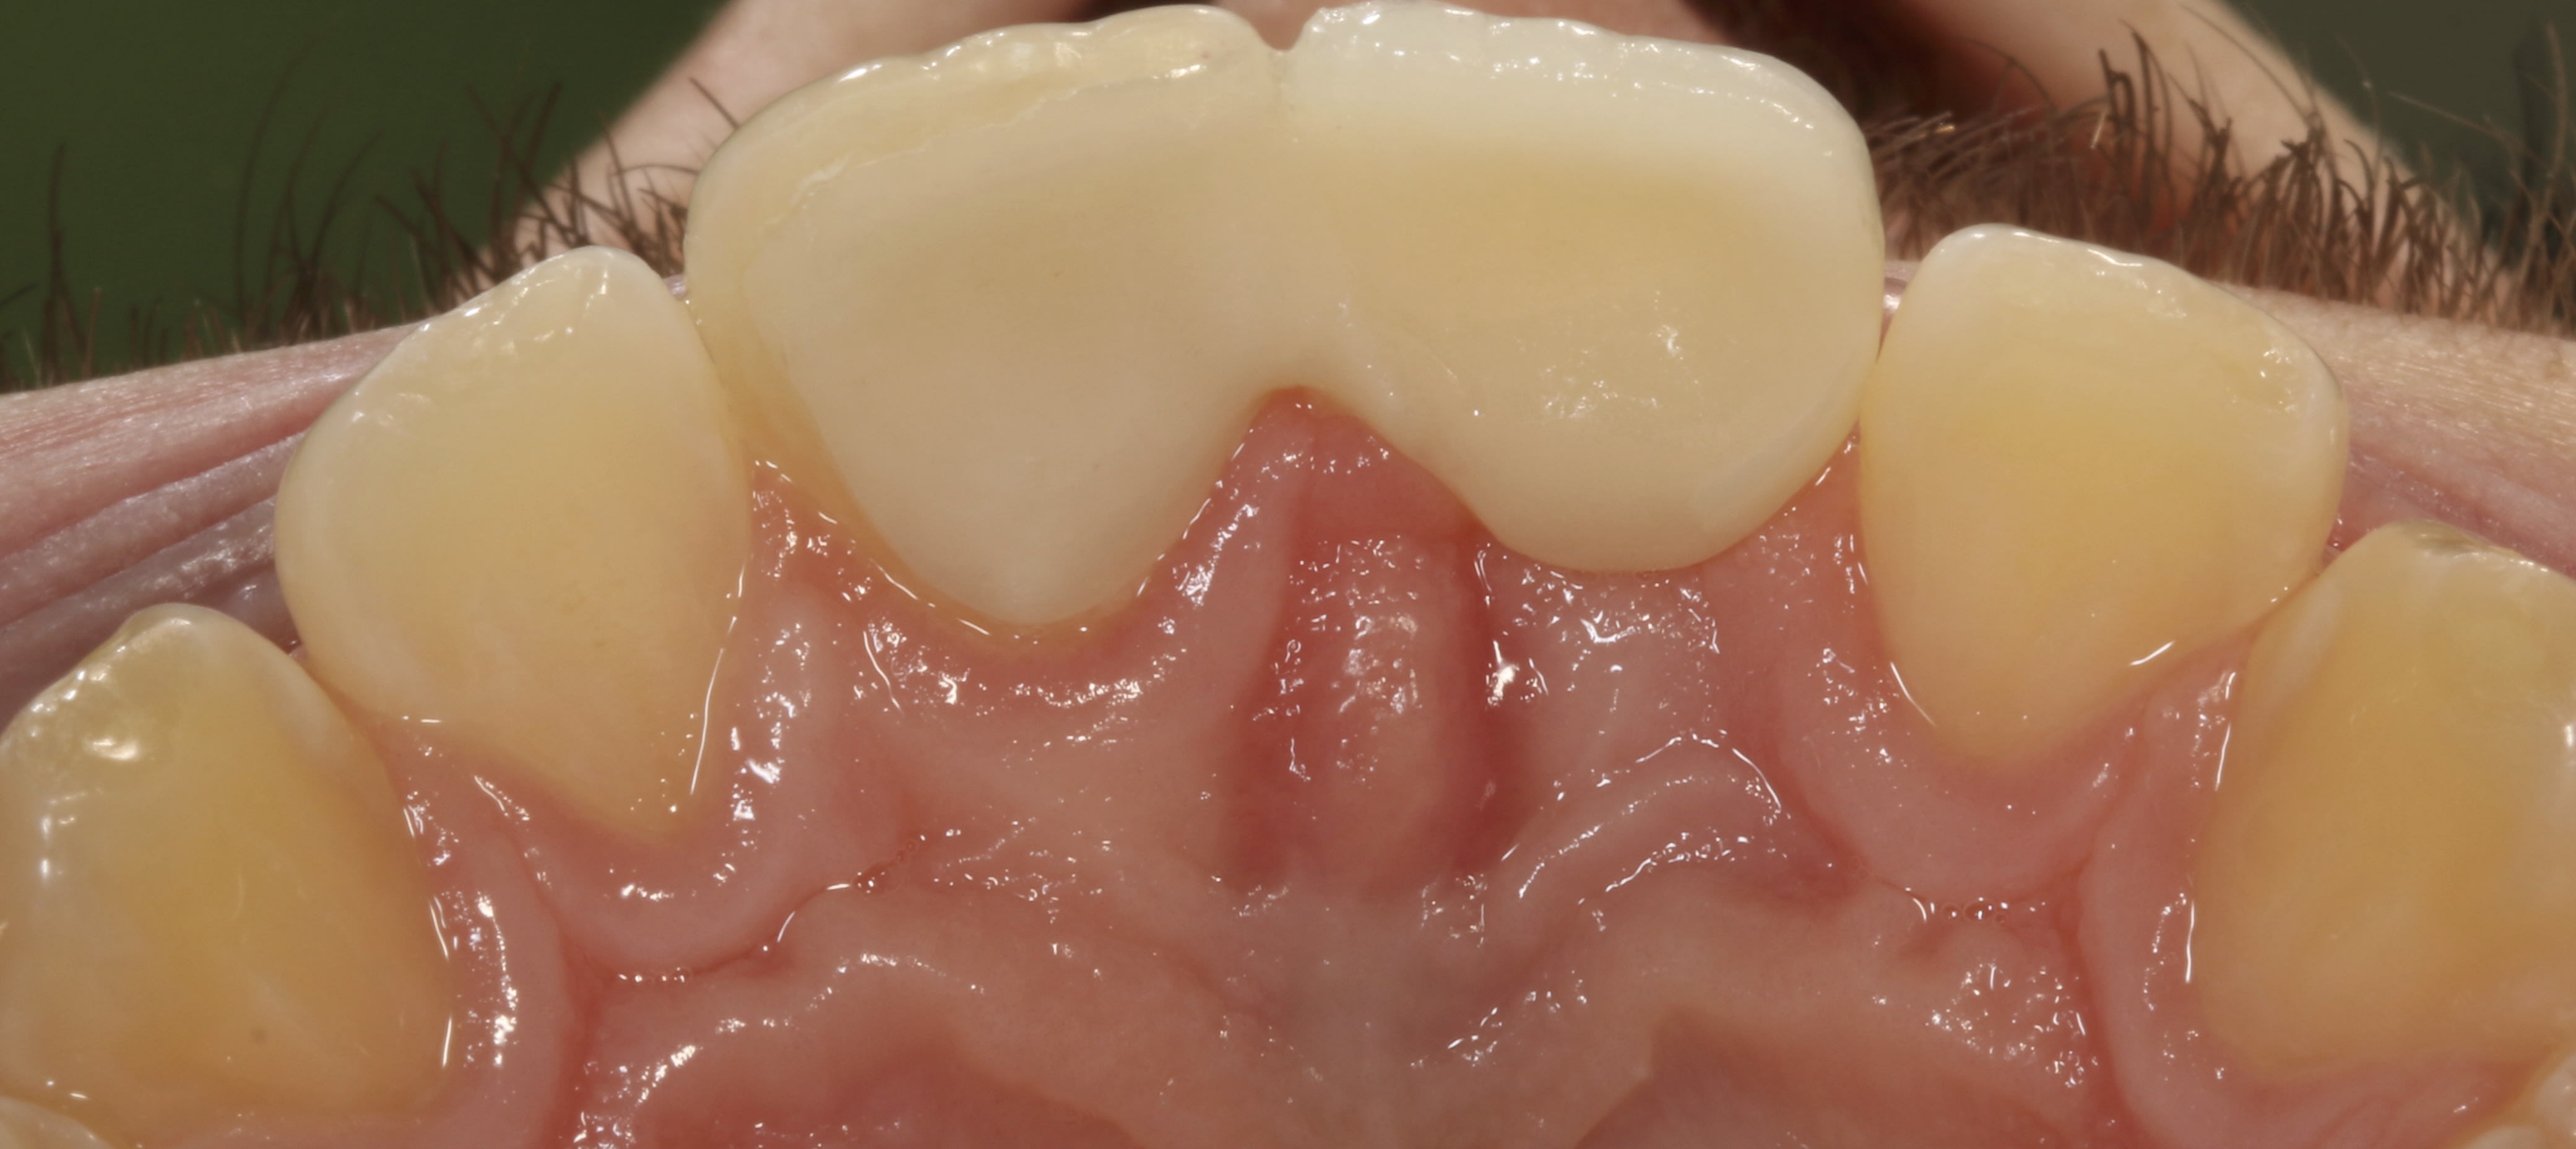

Allé cadeau pour Junior. Avec de la physique on sait encore faire de chouette chose :-). Trouvez Charlie (simple) et qu'est-ce que c'est (moins simple)?

Img 4442 pqt5d6 - Eugenol

c'est la 11, c'est une… facette ?

Non, autre indice il faisait du foot en salle 5 ans plus tôt.

Non mais en mettant la lèvre sur le 1/3 cervical des dents tout le monde peut cacher ce qu’il veut

18 ans, y s'est mangé un mur (pas un arbre lui) 5 ans plus tôt, mais RAS à l'époque.....y s'est passé quoi?